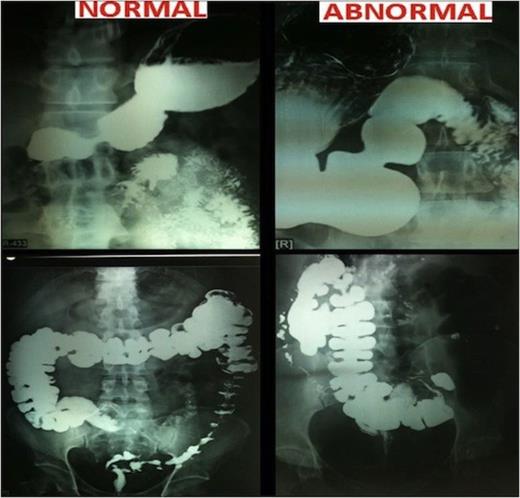

A 32 yr old morbidly obese female weighing 111 Kg and BMI of 41.41 was electively admitted to the hospital. She had tried a number of diet and exercise programmes but failed to sustain reduced weight loss. She was a known case of partial situs inversus as diagnosed earlier during her pregnancy few years ago. She underwent standard pre-operative workup including physician, psychological and anaesthetic assessment satisfying our selection criteria for surgery. This Grade 3 obese patient suffered from cough, dyspnoea and chest pain. She had no history of diabetes or Ischemic heart disease though blood pressure was 130/80 mmHg. Her general examination and preoperative investigations were within normal limits. Heart sounds were normal and on the left side in the chest. Abdominal girth was increased. Preoperative barium follow through under fluoroscopic control showed situs inversus with malrotation of gut. Stomach was on the right side, normal in shape, increased size, normal mucosal pattern, no ulcer. Duodenal C Loop was opposite. Small bowel on right side and normal, no narrowing. Ileocecal junction, caecum and appendix was in left iliac fossa. Descending and sigmoid colon located on the right side close to ascending colon. CT scan of chest/abdomen and pelvis showed enlarged mediastinal lymph nodes and situs inversus. Patient was admitted one day prior to surgery and LSG was performed in January 2011. Following general anaesthesia, patient was placed in reverse Trendelenberg position. Primary operating surgeon stood on the left side of the patient as contrast to usual right side. Trocar positions were also mirror imaged. Operative feel was uncomfortable; as in a right handed person writing by a left hand. Entire upper quadrant was occupied by the liver. Enlarged spleen was in the right side. Orogastric tube negotiation was difficult because of the position of the stomach. Primary surgeon had to come to right side to reach to the right crus. Most of the time single hand technique had to be used instead of both hands. Surgical time was 90 minutes.

Postoperative upper GI contrast study was performed and showed no evidence of leak and a well designed vertical sleeve of the stomach. The post operative period was uneventful and patient was discharged after 4 days. She was given standard advise to remain on liquid diet for 2 weeks, followed by 2 weeks of soft diet, before reintroducing solids. Her present weight is 75Kg and BMI is 28 Kg/m2.